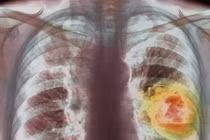

Tại đó, các bác sĩ vẫn nói vết bầm trên đầu Charlie “không đáng lo ngại” và họ nên trở lại đây tái khám sau 2 tuần. Tuy nhiên, gia đình bé đã cương quyết được chụp cắt lớp để yên tâm hơn. Kết quả cho thấy, Charlie mang một khối u 6cm và một khối u khác 12cm trong dạ dày, đồng thời vết sưng trên đầu bé cũng được xác định là một khối u thần kinh đã ở giai đoạn 4 và có kích thước lên tới 7 cm. Ngay lập tức, bé đã đưa tới Bệnh viện Nhi Birmingham để hóa trị. Nhưng bé đã chút hơi thở cuối cùng vào ngày 24/3/2017 sau chuỗi ngày chiến đấu kiên cường tại bệnh viện.